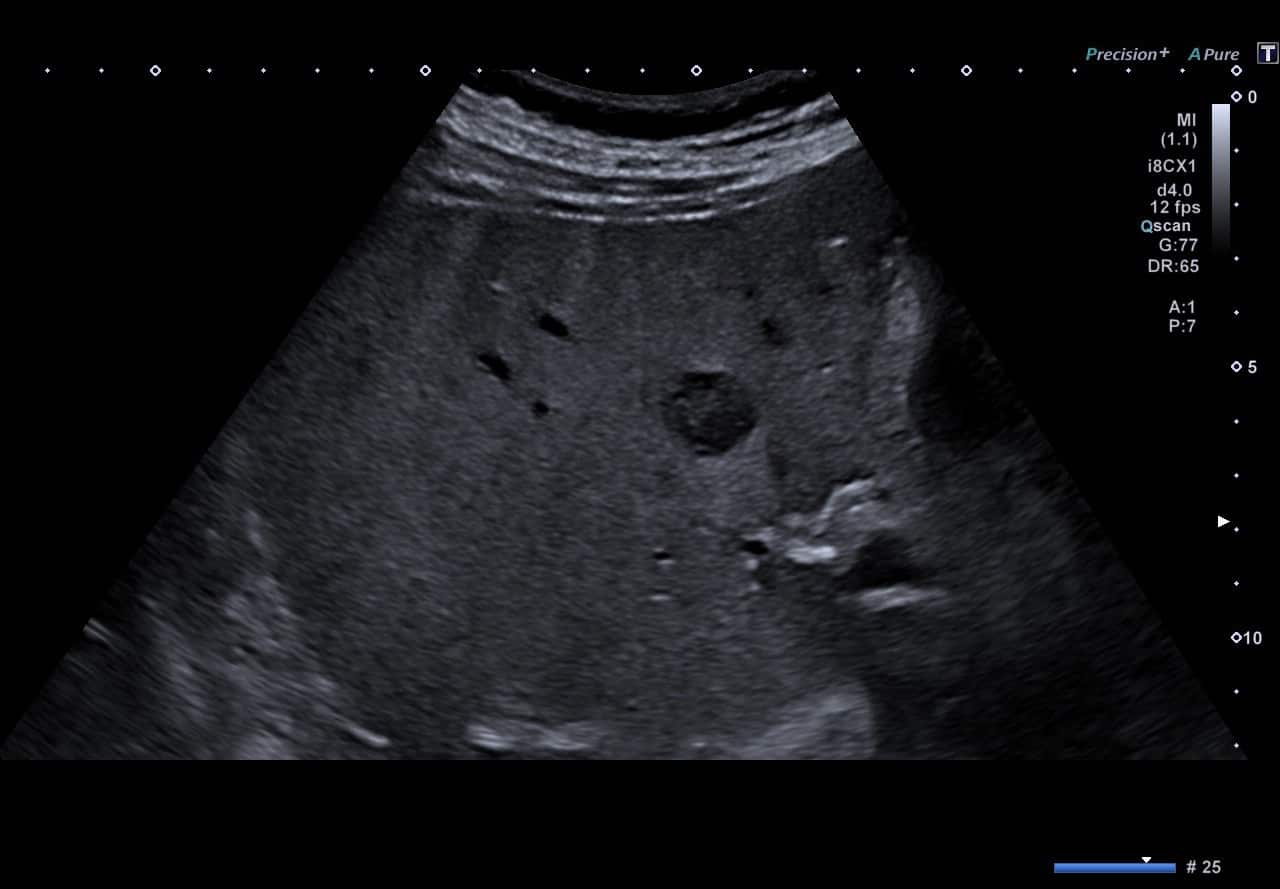

In der Sonografie stellt sich der Befund meist isoechogen zum übrigen Lebergewebe dar. Bei Zugabe eines Ultraschall-Kontrastmittels wird die radspeichenartige Gefäßversorgung dargestellt. Durch das isodense bzw. isointense Verhalten in Computertomographie bzw. Magnetresonanztomographie ist der Befund schwer zu entdecken. Nach Kontrastmittel-Gabe mit wasserlöslichen Kontrastmitteln zeigt sich bei diesen Verfahren ein randständig starkes Kontrastmittel-Enhancement mit zentraler Hypodensität bzw. Hypointensität. Durch die Verwendung gallegängiger Kontrastmittel (Gadoxetic Acid = Primovist (R)) kann in der Magnetresonanztomographie in einer Spätphase mit hoher Empfindlichkeit eine Differenzierung erreicht werden.[1]